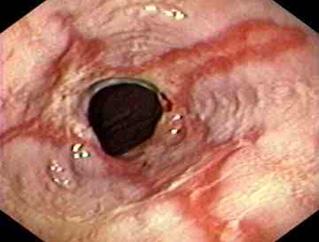

Figura 6. Esofagitis erosiva. Son visibles múltiples Figura 7. Esófago de Barret es una lesión premalgina. Metaplasia → displasia → adenocarcinoma (tercio inferior del esófago) (ENAM 2020)

úlceras y erosiones lineales y redondas (algunas de color rojo más oscuro, algunas cubiertas por un exudado fibrinoso gris).

♦ Segmento largo (> 3 cm) → mayor riesgo de cáncer (adenocarcinoma)